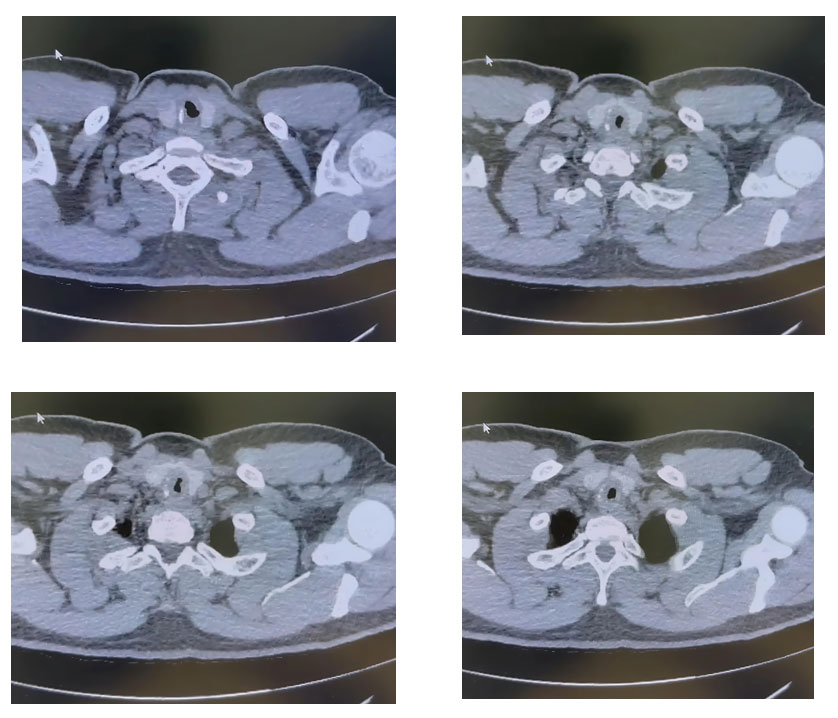

A CT Neck and Chest revealed a severe short-segment tracheal narrowing at the C7 level, suggestive of subglottic stenosis.